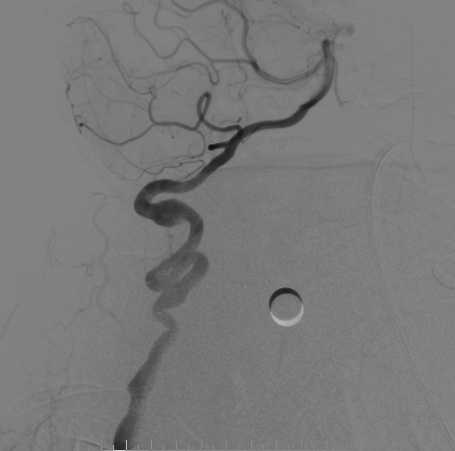

手术过程

右侧桡动脉穿刺置入6F 泰尔茂薄壁鞘,Cat5中间导管同轴rebar27导管头端塑形在0.014微导丝引导下引至右侧颈内动脉海绵窦段,Cat5中间导管引入V18导丝加强系统支撑。

畅医达(Accessway)0.017支架微导管在0.014微导丝引导下顺利到达右侧大脑中动脉M2远端,经支架微导管引入畅医达(Choydar)血流导向装置,3mm*15mm,推送平顺,然后跨瘤颈缓慢释放支架,支架头端打开良好。

支架部分释放后复查造影示支架位置良好,缓慢完全释放支架,支架打开良好,复查造影示支架位置良好,完全覆盖瘤颈,贴壁佳,瘤囊内可见造影剂滞留明显,OKM分级A3。